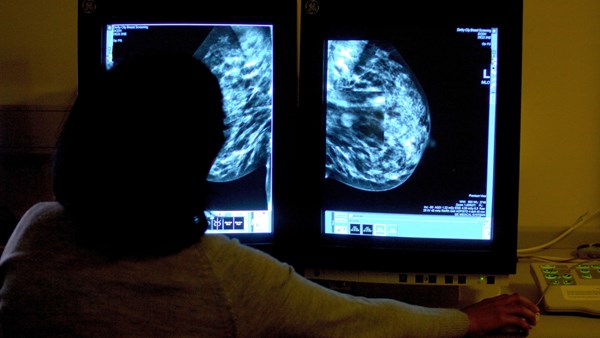

The TAILORx trial used the Oncotype DX test which allows doctors to predict the likelihood of the breast cancer returning.

A sample of the tumor is tested after surgery for 21 genetic markers, which indicate if it could grow and spread.